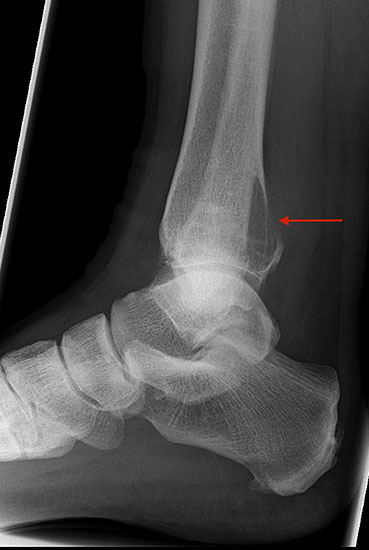

Die beiden häufigsten primären malignen Knochentumoren überhaupt, das Osteosarkom und Chondrosarkom, finden sich neben dem Ewing-Sarkom auch im Bereich des Fußes am häufigsten. Diese Tumoren können sich klinisch wie auch bildgebend sehr variabel darstellen, was die hohe Anzahl von Fehldiagnosen und verzögerten Diagnosestellungen erklären kann 25. Osteosarkome treten im Bereich des Fußes im Vergleich zu den typischen Lokalisationen (kniegelenksnah) durchschnittlich ca. 10 Jahre später auf (Abb. 15). Der Calcaneus ist die bevorzugte Lokalisation für Osteosarkome des Fußskeletts und ein Großteil dieser Tumoren ist schlecht differenziert (G3) 46. Das Verteilungsmuster des Ewing-Sarkoms ist noch heterogener. In einer Nachuntersuchung von 1997 zeigten sich 6 von 16 Ewing-Sarkomen im Bereich der Metatarsalia, 4 in den Phalangen, 3 im Calcaneus und jeweils eines im Talus und eines im Os navikulare 47. Das durchschnittliche Patientenalter unterscheidet sich nicht von den herkömmlichen Lokalisationen. Auffällig ist jedoch die erhebliche Diagnoseverzögerung. So vergehen bei einem Ewing-Sarkom-Befall des Fußes durchschnittlich 14 Monate von Beginn der Symptome bis zur korrekten Diagnosestellung, bei Lokalisation im Rückfuß sind es gar 22 Monate (Abb. 28). Die Therapie des Ewing- und Osteosarkoms des Fußes unterschei­det sich grundsätzlich nicht von der etablierten Behandlungsstrategie dieser Tumoren und umfasst in der Regel die neo-adjuvante Chemotherapie, weite Tumorresektion und anschließende adjuvante Chemotherapie. Die Strahlentherapie besitzt in der Behandlung des Ewing-Sarkoms unverändert einen hohen Stellenwert. Ewingsarkome sind definitions­gemäß stets schlecht differenziert (G3 bzw. G4), also hoch maligne. Das operative Vorgehen ist dieser Tatsache anzupassen.